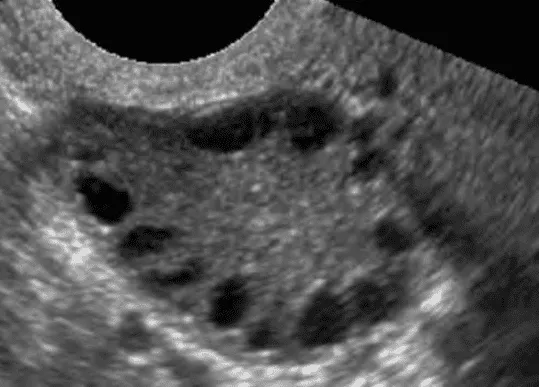

Phần tiêu đề “Chẩn đoán hình ảnh”Có thể thực hiện siêu âm quy ước để khảo sát độ dày nội mạc tử cung, phản âm, bất thường trong buồng tử cung.

Hình ảnh “Chuỗi hạt kinh điển của buồng trứng đa nang. Các nang noãn nhỏ xếp thành chuỗi, phân bố ở ngoại vi buồng trứng”.